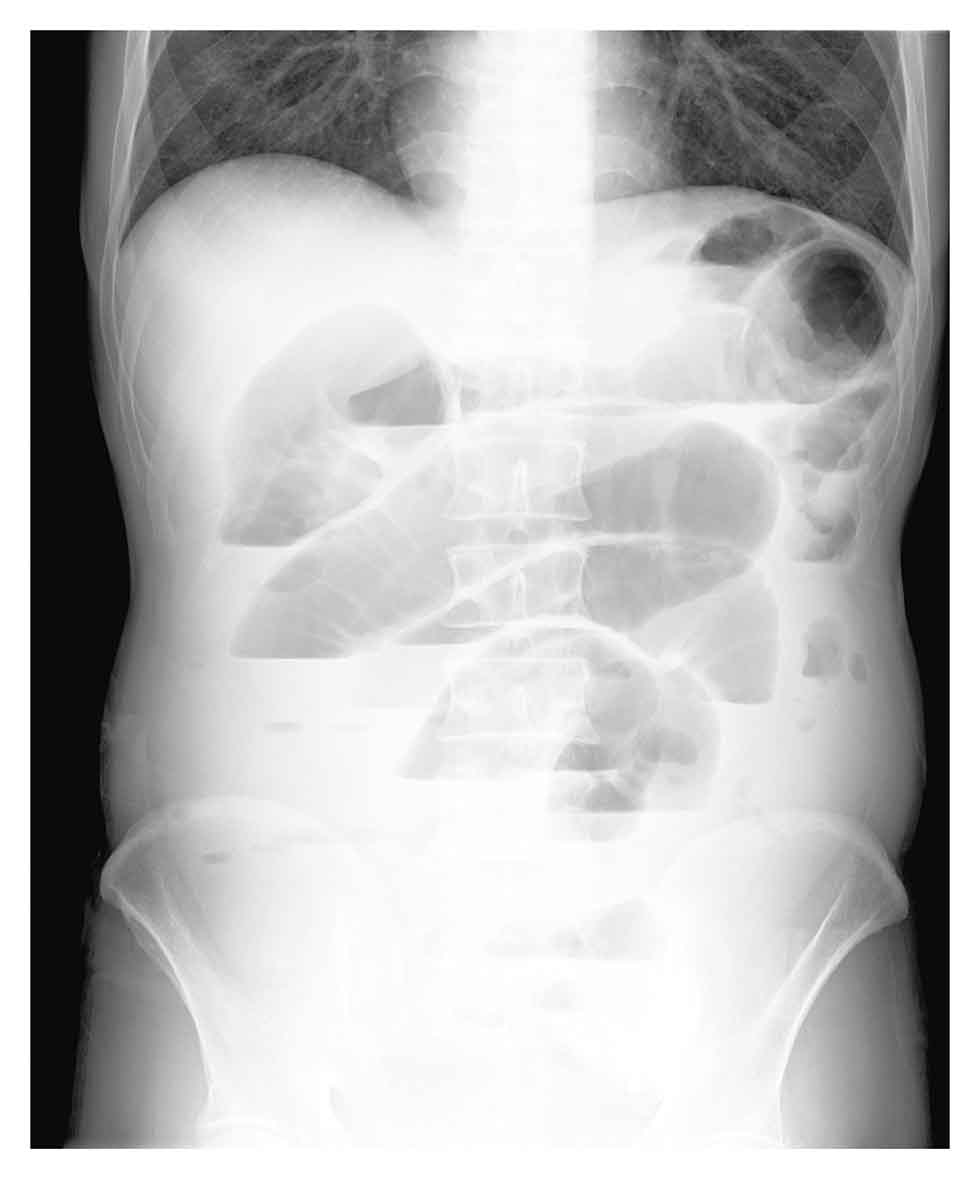

イレウス 腸閉塞 を理解して 腹部x線写真 レントゲン のポイントを押さえる 読影を中心にradiographica 診療放射線技師のバイブル

第3回 イレウス イレウスの腹部単純写真がきわめてよく出題されている 診断は 典型的なニボーを伴う 小腸ループの拡大でわかる 問われるのは 患者の治療方針をどうするかが多いようである ポイント 単純性 癒着性 か絞扼性かを見きわめる

臥位の腹部x線でもイレウスを発見できる 日経メディカル